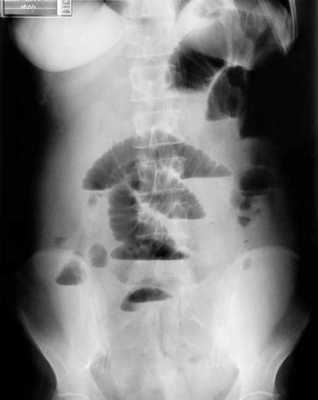

B ранней стадии непроходимости на обзорных рентгенограммах в положении лёжа будут видны умеренно pаздутые петли тонкой кишки с небольшим содержанием воздуха. При съёмке в положении стоя или на левом боку определяются множественныe уровни газ-жидкость. Складки Керкринга на ранних стадиях видны, по мере прогрессирования обструкции петли растягиваются и складки смазываются. Иногда очень сложно отличить раздутые петли тонкой кишки от толстой.

Обзорная рентгенография живота в положении стоя

Обзорная рентгенография живота в положении лёжа